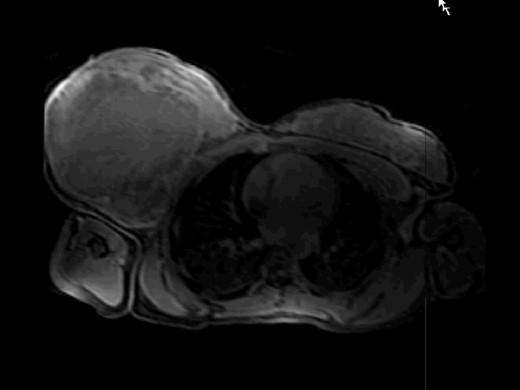

An 18-year-old African female patient with no relevant past or family history was admitted at our hospital due to a 34-cm tumor on the right breast (Fig. 1). The patient, from Cape Verde, delayed her appointment with a doctor because she could not afford to miss a day at work. When she finally went to the doctor, due to rapid growth of the mass, the tumor was extremely large, and she was immediately evacuated to Portugal. Biopsy showed an extensively necrotic MBC, triple negative, with Ki67 >90%. Thorax, abdomen and pelvic CT showed axillary lymph node involvement, without other secondary foci. Breast MRI showed probable muscle infiltration (Fig. 2). A multidisciplinary team decided that a modified right radical mastectomy should be performed (Fig. 3).

MRI T1f study after paramagnetic contrast showing a large mass occupying the entire right breast with extensive central necrosis.